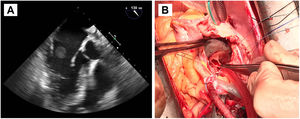

Hombre que 17 años de edad con antecedente de resección de teratoma pineal hace siete años. Presentaba una recidiva del teratoma pineal, detectándose en el estudio preoperatorio un FOP. Se decidió cierre del mismo de forma percutánea por vía venosa femoral con un dispositivo de 20 mm, sin complicaciones, para evitar embolismos paradójicos ante necesidad de reintervención neuroquirúrgica por craniectomía suboccipital en posición de sedestación. Seis meses después del implante del dispositivo y un mes y medio tras la resección del teratoma recidivado, con estudio oncológico libre de enfermedad, presentó un síndrome febril con hemocultivos positivos para Staphylococcus aureus meticilín-sensible, iniciándose tratamiento con cloxacilina y daptomicina. No se encontraron hallazgos en la ecocardiografía transtorácica, excepto una insuficiencia tricúspide ligera-moderada no presente previamente al implante del dispositivo, pero se evidenció en la ecocardiografía transesofágica una masa filamentosa móvil, de 1,9 cm, adherida al disco de aurícula derecha del dispositivo de cierre de FOP, próxima a la desembocadura de la vena cava superior, compatible con vegetación sobre el dispositivo (fig. 2A). Dado el tamaño de la vegetación y el germen identificado, se decidió cirugía urgente.

A: Ecocardiografía transesofágica preoperatoria. Se evidencia una masa filamentosa móvil adherida al disco de aurícula derecha del dispositivo de cierre de FOP, próxima a la desembocadura de la vena cava superior, compatible con vegetación sobre el dispositivo. B: Fotografía del campo quirúrgico. Atriotomía derecha para acceso al septo interauricular donde se encuentra anclado el dispositivo de cierre de FOP, con endotelización completa. Resección del dispositivo objetivándose en la vertiente auricular derecha la vegetación filamentosa. C: Resonancia magnética cardiaca postoperatoria. Se aprecia el engrosamiento pericárdico sobre pared ventricular con captación de contraste sugestivo de inflamación.

Bajo circulación extracorpórea y pinzado aórtico, se retiró el dispositivo con la vegetación anclada a la cara auricular derecha, requiriendo la reconstrucción del septo interauricular con parche de pericardio heterólogo (fig. 2B). Como habitualmente se hace, la cirugía se realizó bajo monitorización con ecocardiografía transesofágica, con resultado postoperatorio sin valvulopatías y con buena función biventricular, sin cortocircuito residual. No obstante, posteriormente se evidenció en la ecocardiografía transtorácica de control una insuficiencia tricúspide libre producida por falta de movilidad de los tres velos, de forma prácticamente simétrica, sin alteración estructural de los mismos, aparentando de funcional, pero sin asociar disfunción ni dilatación ventricular derecha significativa, ni otra alteración. El paciente se encontraba completamente asintomático, por lo que tras tres días de tratamiento depletivo, se repitió el estudio. Se encontró la insuficiencia tricúspide ligera-moderada como preoperatoriamente, con discreta disminución del diámetro ventricular derecho, pareciendo por tanto relacionado a sobrecarga de volumen en el postoperatorio inmediato.

Evolución posterior satisfactoria. Sin embargo, reingresó tras finalizar tratamiento antibiótico ambulatorio por disnea a moderados esfuerzos con derrame pleural derecho que requirió toracocentesis. Presentaba elevación de marcadores analíticos inflamatorios y se evidenciaba nuevamente aumento de la insuficiencia tricúspide asociado a desplazamiento septal inspiratorio secundario a posible fisiología constrictiva, sin dilatación de la vena cava inferior. Se completó estudio con resonancia magnética cardiaca, que objetivó derrame pericárdico ligero global y engrosamiento pericárdico con captación de contraste, sugestivo de pericarditis constrictiva inflamatoria posquirúrgica (fig. 2C). Los hemocultivos fueron negativos. Se inició tratamiento antiinflamatorio con excelente respuesta clínica y de marcadores analíticos, por lo que junto a la captación de contraste pericárdico como predictor de buena respuesta, se manejó de forma conservadora, pendiente de evaluar evolución a largo plazo6.